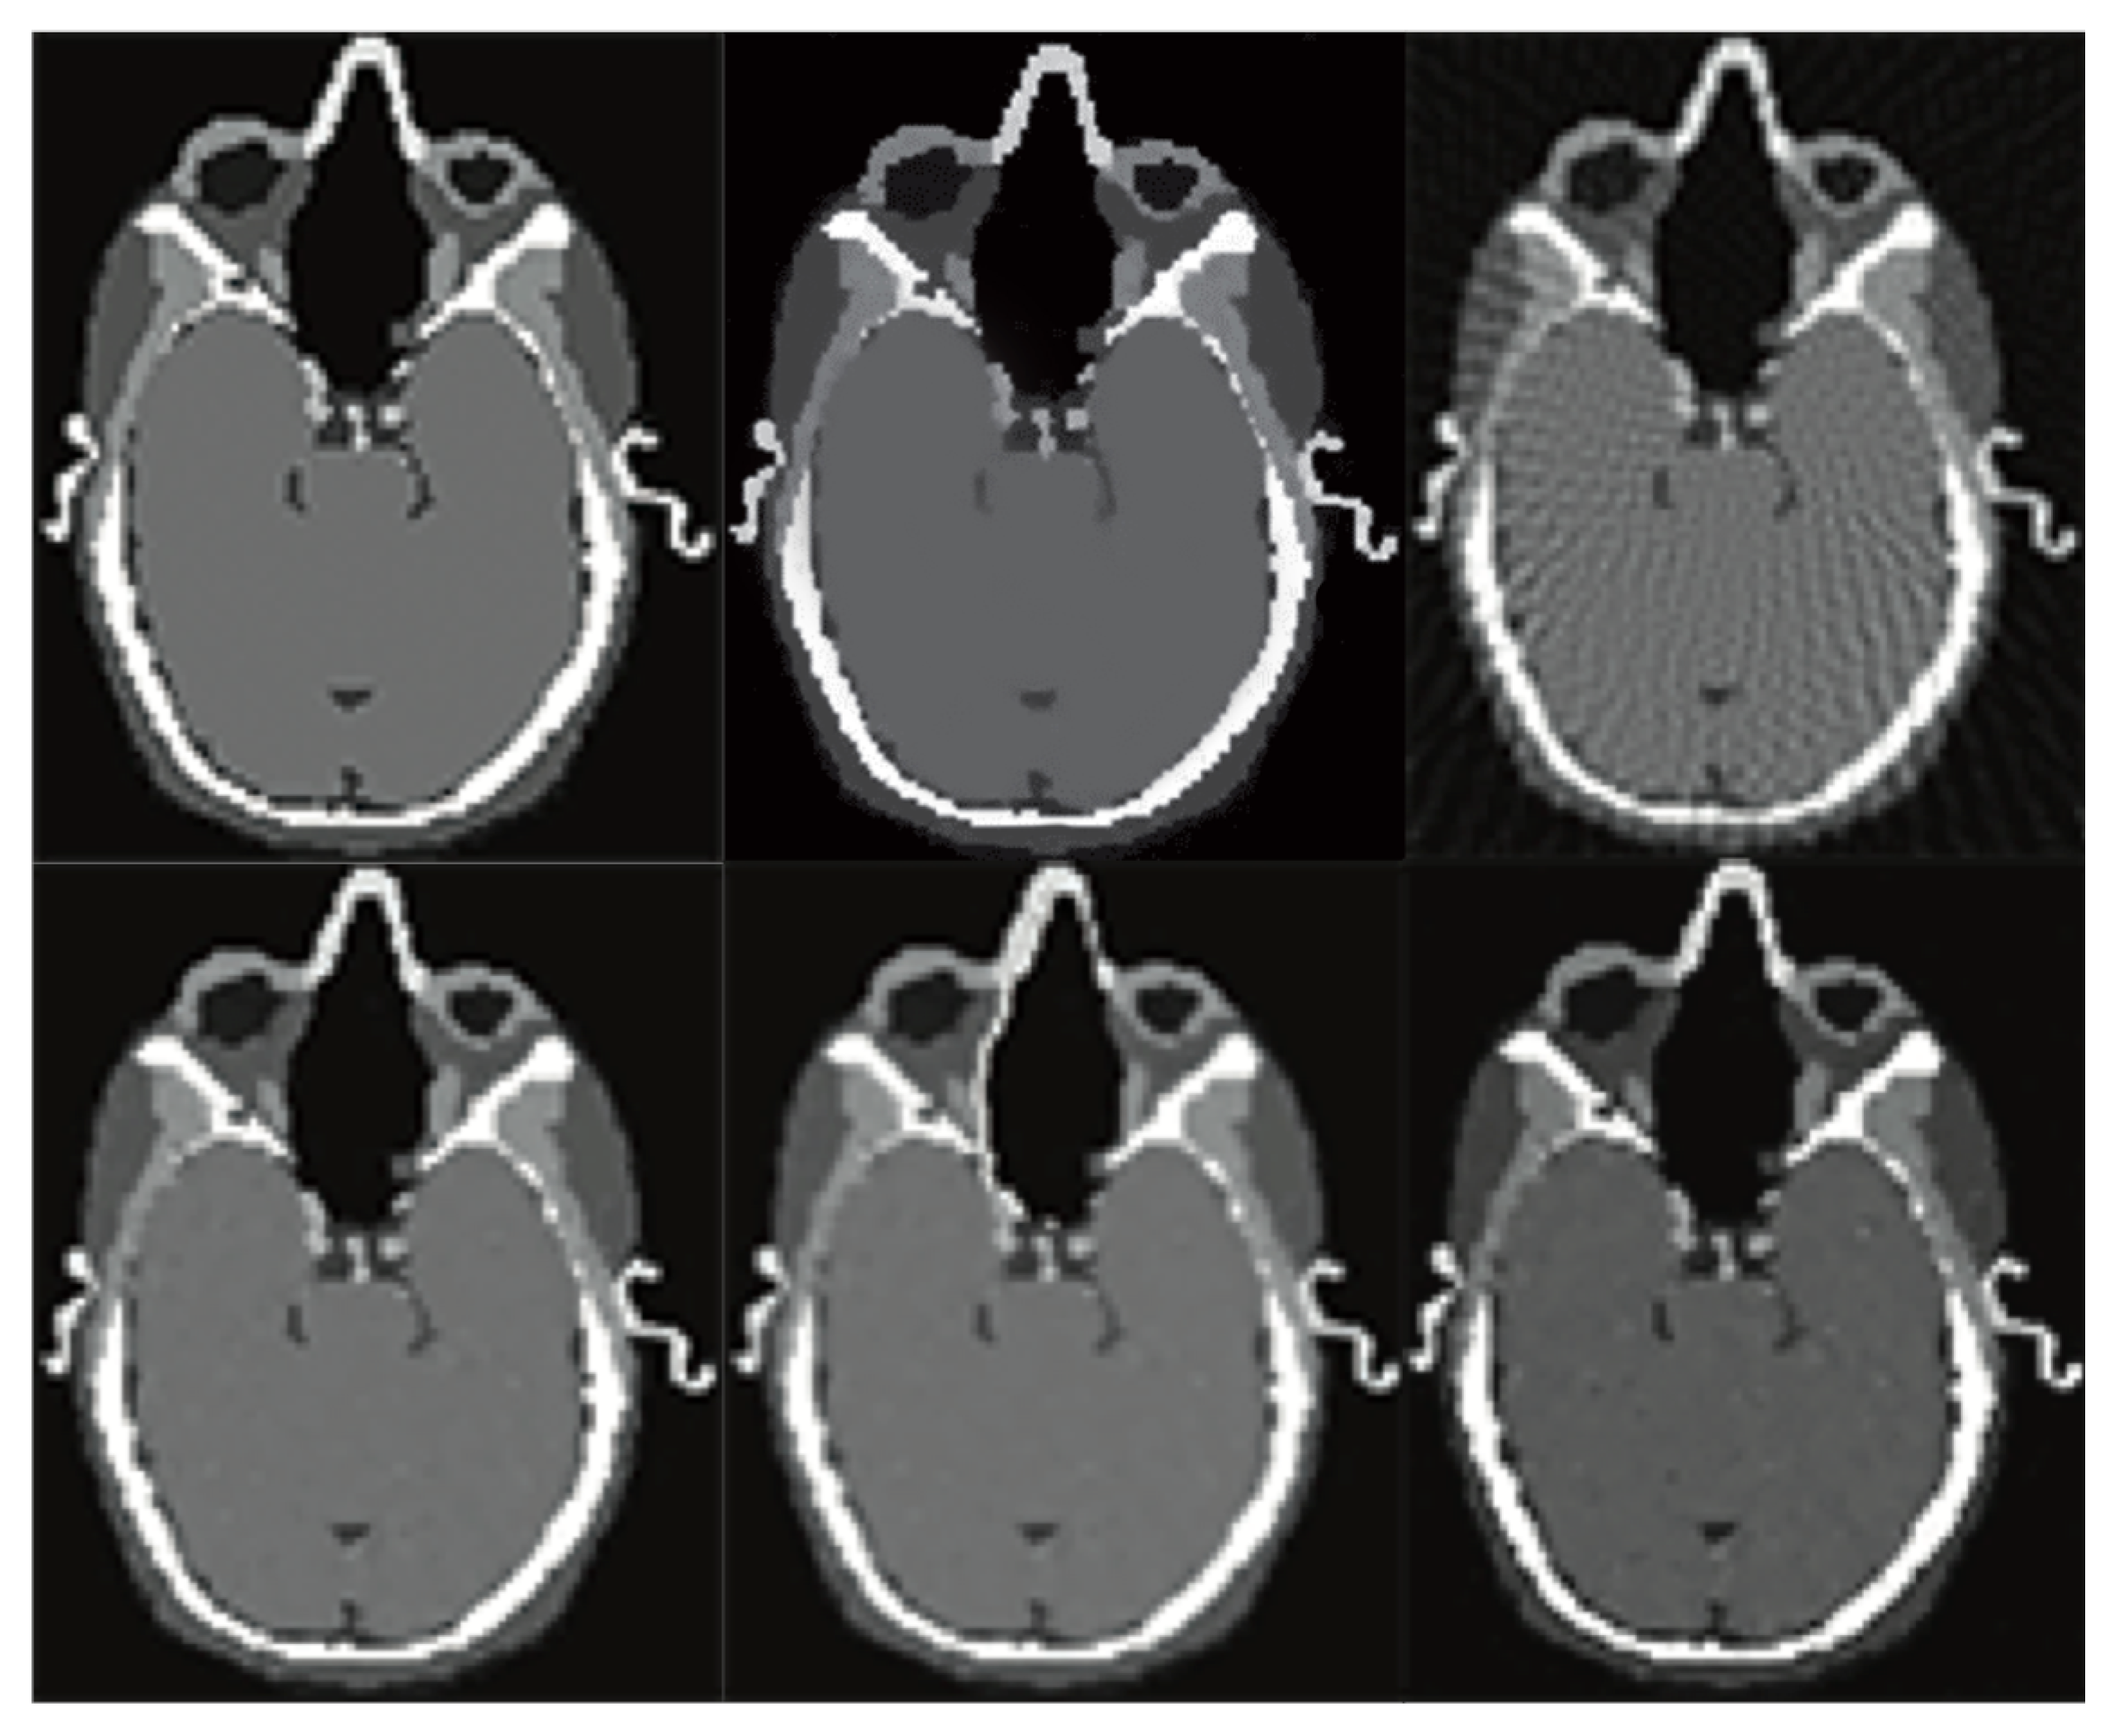

Figure 5.

The XCAT phantom images based experiment results. The upper row: two CT scans with simulated motion artefacts. The bottom row shows the super-resolution CT scan.